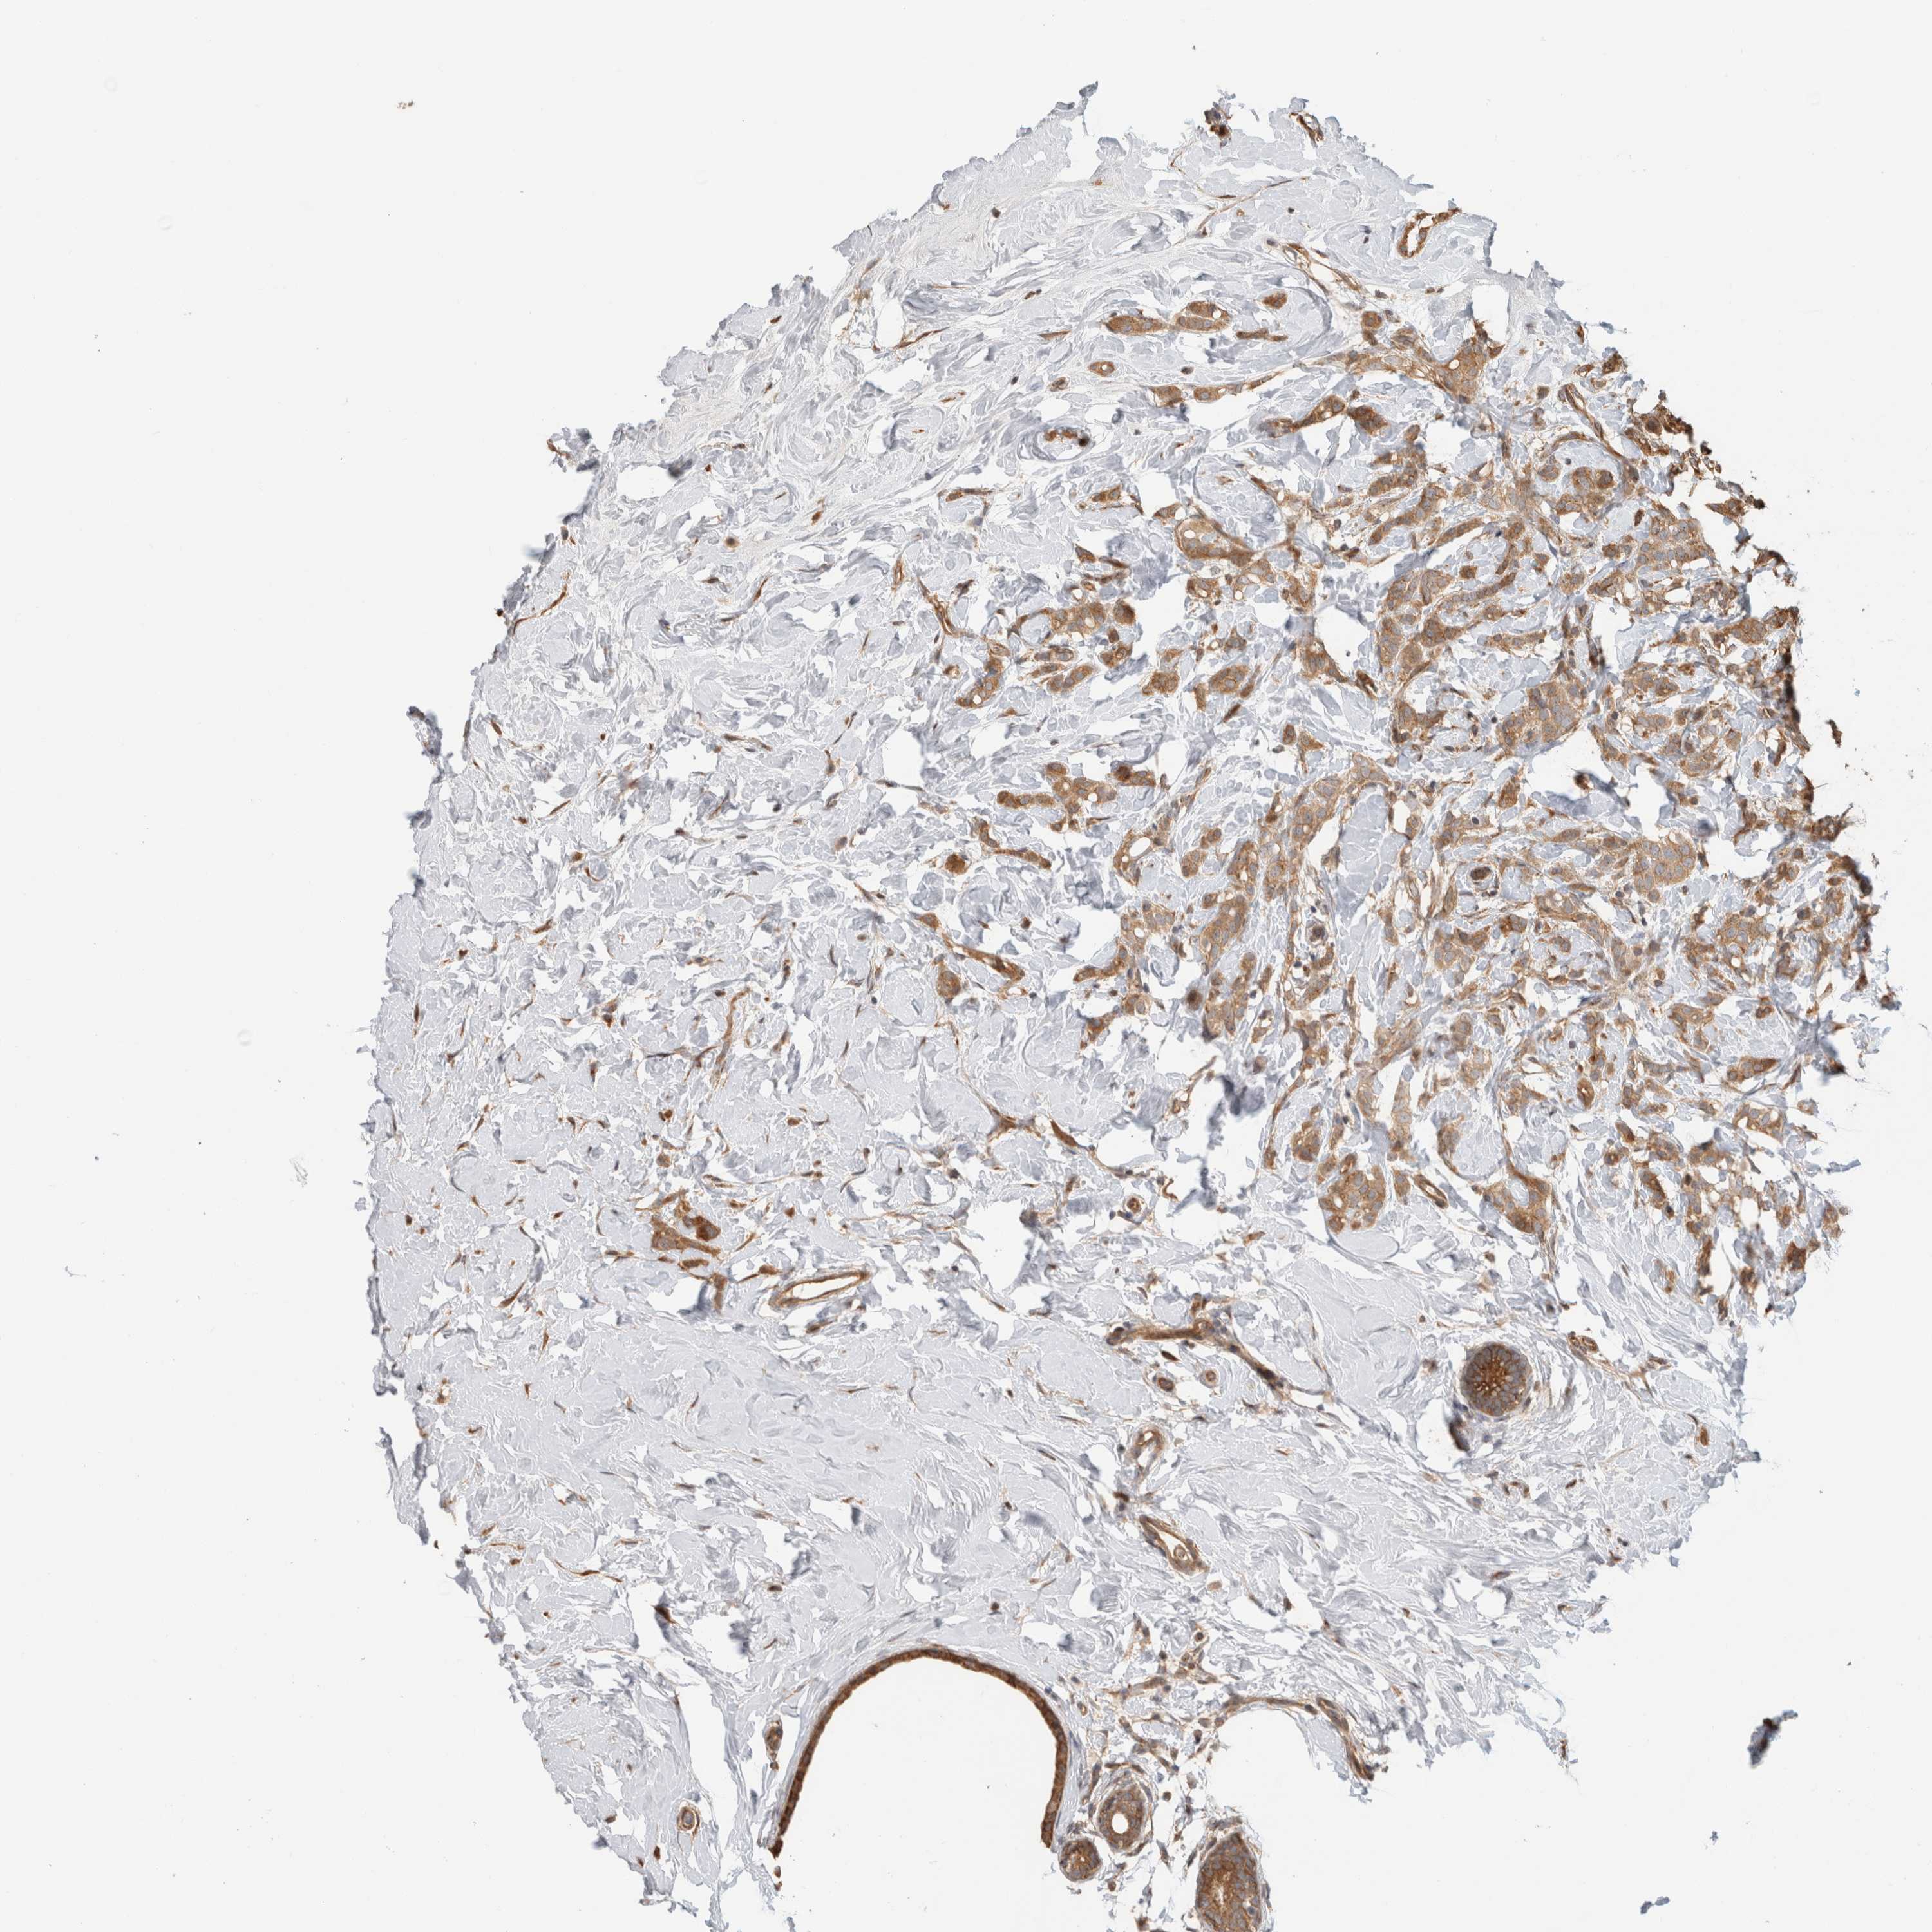

CANCER BREAST CANCER Show tissue menu

BRCA TCGA BRCA VALIDATION PROTEIN EXPRESSION